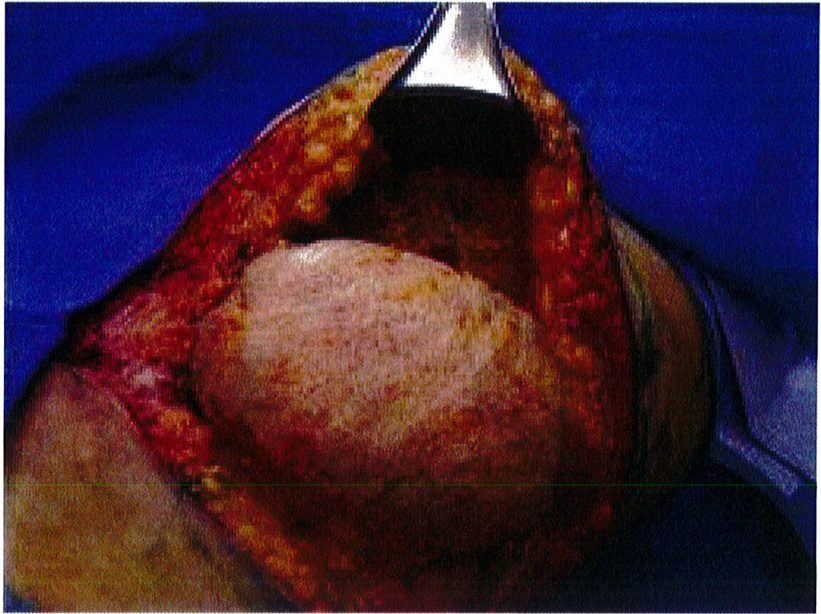

Hệ thống cân nông có thế được đánh dấu sau khi đã bộc lộ để xác định dễ dàng hơn, đồng thời các đường khâu cũng chính xác hơn. Sau đó dùng chỉ Mersilene số 1 khâu lớp cân nông lại với nhau và siết chặt chỉ để tạo thành một khối hình cầu (Hình 6). Kết quả thu được sẽ tương tự như khi bệnh nhân được đặt một khối implant cỡ lớn, với điểm hình chiếu tốt (Hình 7). Sau đó chúng được neo vào lớp cân nông phía trong (cạnh xương cùng) đã được bảo tôn trước đó. Lúc này có thể dùng chỉ Mersiline 3 (Hình 8). Cho tới nay không ghi nhận một trường hợp ứ máu hay tắc nghẽn ở tĩnh mạch vùng mô trung tâm nào.

ở hình 5) được khử biểu mô bằng dao tay hoặc dao điện để bộc lộ tới phần cân nông. Phần ranh giới của mô trung tâm này được bóc tách tới lớp cân cơ, làm chúng bị cô lập với các tổ chức xung quanh. Sau đó sử dụng mũi purse-string khâu đính phần cân nông lại với nhau rồi thít chặt chỉ để hình thành nên một đảo chứa các tổ chức dưới da, cân cơ (Hình 6), đồng thời bảo tồn được toàn bộ mạch máu thần kinh phía bên dưới. Chúng ta có thể thấy kỹ thuật này không phá hủy mô quá nhiều, đồng thời có thế sử dụng chính tổ chức dưới da đế tạo ra điểm hình chiếu thẩm mỹ cho mông. Mũi khâu dây rút cũng rất hữu hiệu ở đây vì chúng giúp co các mối chỉ cùng nhau, từ đó dồn và đẩy mô trung tâm lên thành một khối hình cầu, như đang sử dụng một khối implant vậy!

Hình. 5. Khử biểu mô vạt mông. Ở vùng ranh giới tiến hành bóc tách sâu tới lớp cân sâu, bảo tồn các tổ chức mạch máu thần kinh. Da chỉ được khử lớp biểu mô để bảo tồn thể tích và tạo ra một mỏ neo vững chắc cho đường giữa.

Hình. 6. Đặt các mối khâu purse-string (như khâu túi dây rút) ở lớp cân nông. Mersilene 1 hoặc tương đương được sử dụng trong khâu này, chỉ khâu phải lướt dễ dàng qua các tổ chức.

Hình. 7. Chỉ khâu được đảm bảo thắt chặt với khoảng 6 nút thắt. Sau khi thít chỉ thì trông mô trung tâm sẽ nhô ra nhiều hơn, là cơ sở để tạo ra điểm hình chiếu sau này.